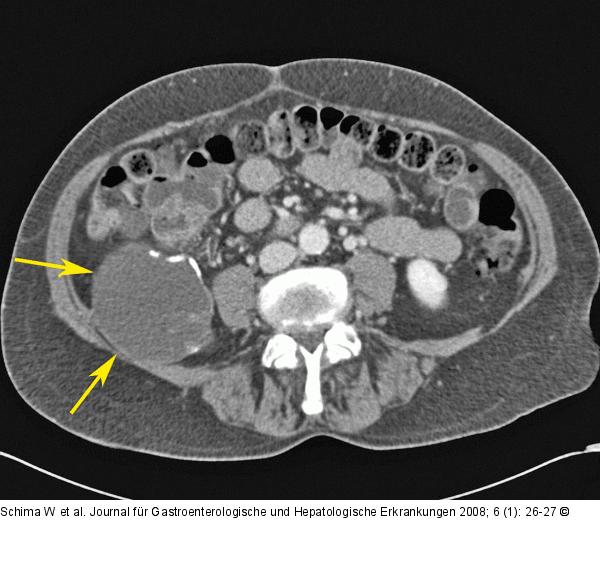

Abbildung 1a: Mukozele Die axiale MDCT zeigt einen wandverkalkten zystischen Tumor (Pfeile) im rechten Unterbauch, der Mukozele der Appendix entsprechend. |

Die axiale MDCT zeigt einen wandverkalkten zystischen Tumor (Pfeile) im rechten Unterbauch, der Mukozele der Appendix entsprechend. |